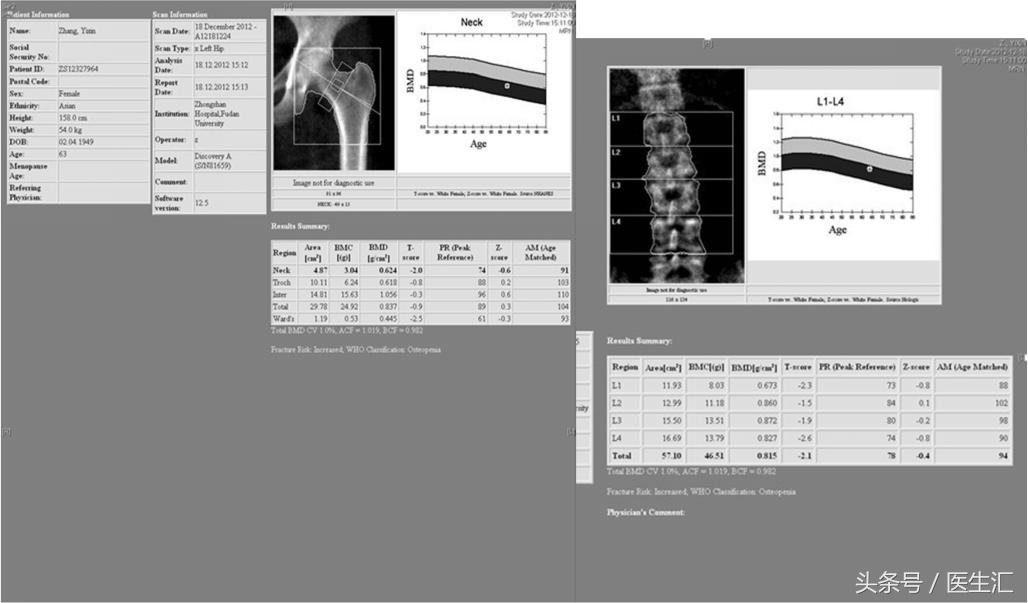

骨密度测定:股骨及腰椎骨量均减少;

DXA骨密度检测